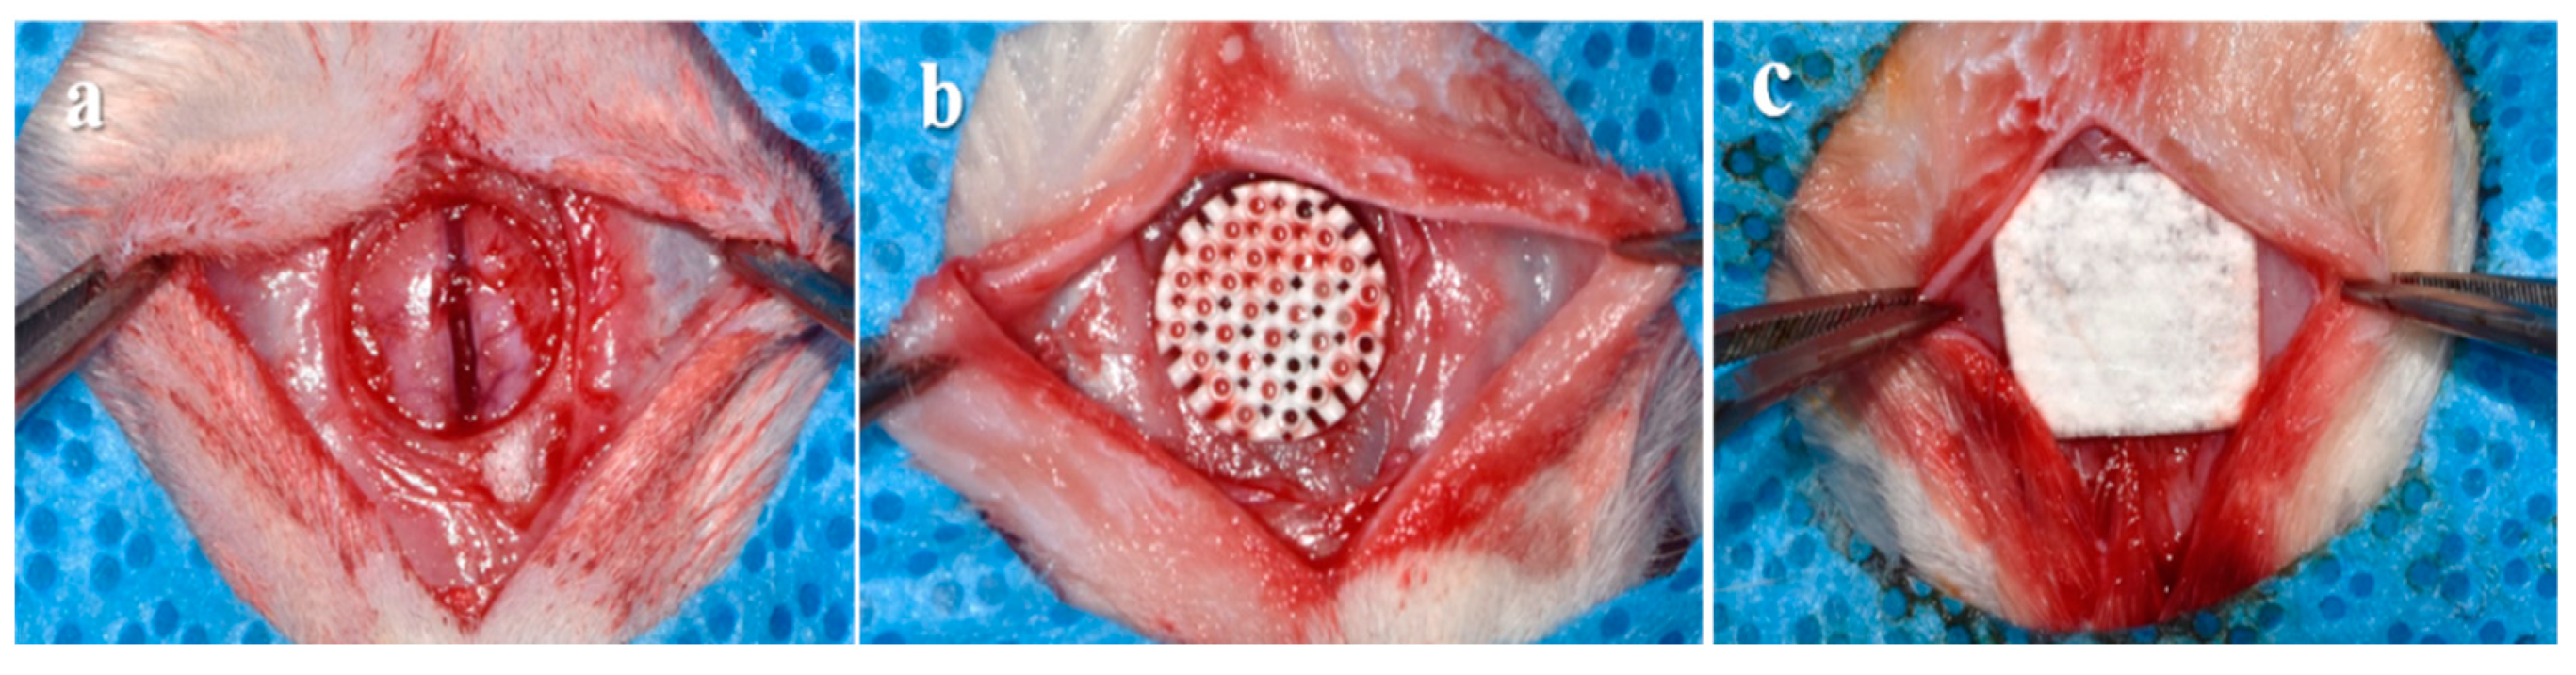

2.3.2. Surgical Procedures